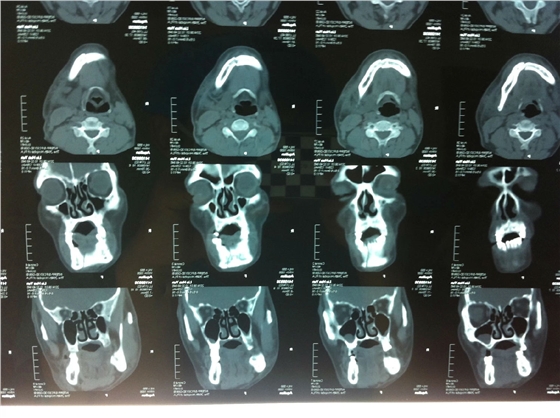

入院后全麻下手術治療,左側下頜骨囊腫較大,術前考慮病理性骨折可能,準備鈦釘鈦板固定,術中摘除囊腫后,發(fā)現(xiàn)下頜骨下緣骨量尚可,未給予固定。術后病理診斷為下頜骨角化囊腫,考慮到患者可能為基底細胞癌綜合征,術中切除頸部皮膚痣兩處,術后病理診斷為:皮膚痣,排除基底細胞癌綜合征?;颊哂凶髠鹊诹吖欠植胬?,綜合以上特征,最終診斷為多發(fā)性頜骨囊腫綜合征。